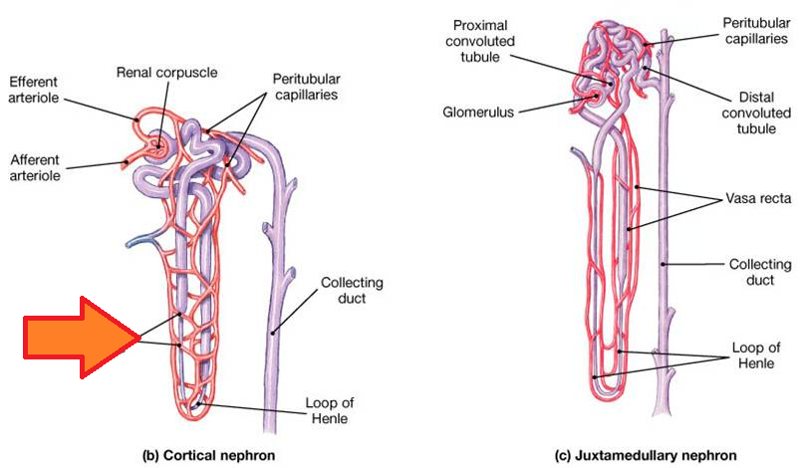

Afferent/efferent arteriole

Collecting duct

Descending/Ascending loop (of nephron)

Distal (convoluted) tubule

Glomerular capsule (=Bowman's capsule)

Glomerulus (=glomerular capillaries)

Juxtaglomerular apparatus

Nephron

Peritubular capillaries

Proximal (convoluted) tubule

Renal corpuscle